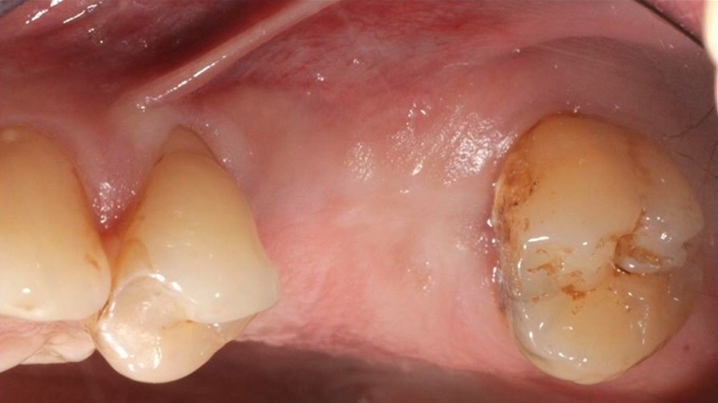

Clinical case: # 46 implant placement & GBR using i-Gen membrane for significant vertical resorption & mixed bone defect

- Courtesy of Dr. Iulian Filipov, Romania -

AnyRidge, mandibular posterior, i-Gen, resorption, bone defect, bone regeneration, space management, #46, GBR, Dr. Iulian Filipov